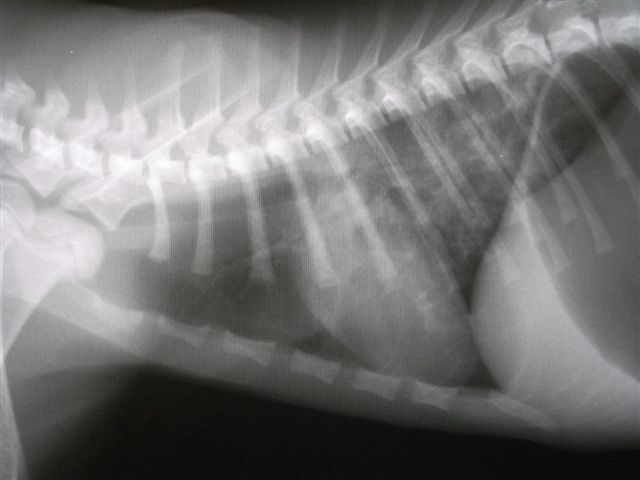

3ヶ月齢の子猫のレントゲン写真

呼吸困難のために胃に大量の空気を飲み込んでる

肺後葉には肺炎で水分がたまって白くにごっている